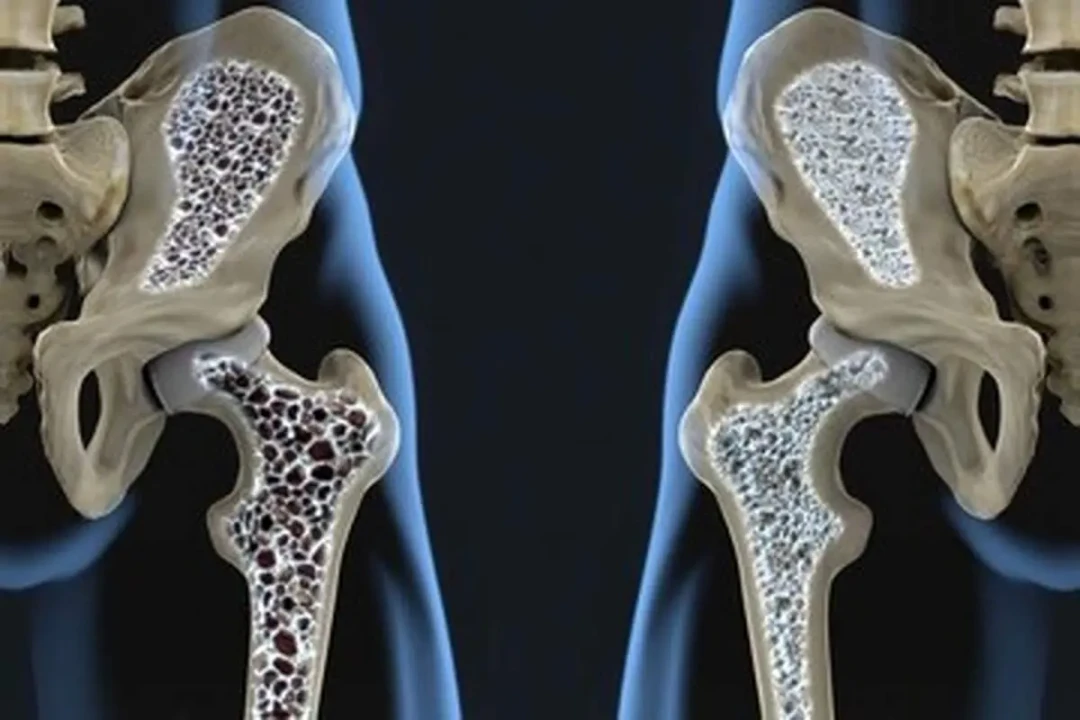

مواد مغذی مهم دیگری هم در تخممرغ وجود دارند؛ ویتامین D که برای سلامت استخوانها، دندانها و عضلهها ضروری است، سلنیوم و همچنین کولین.